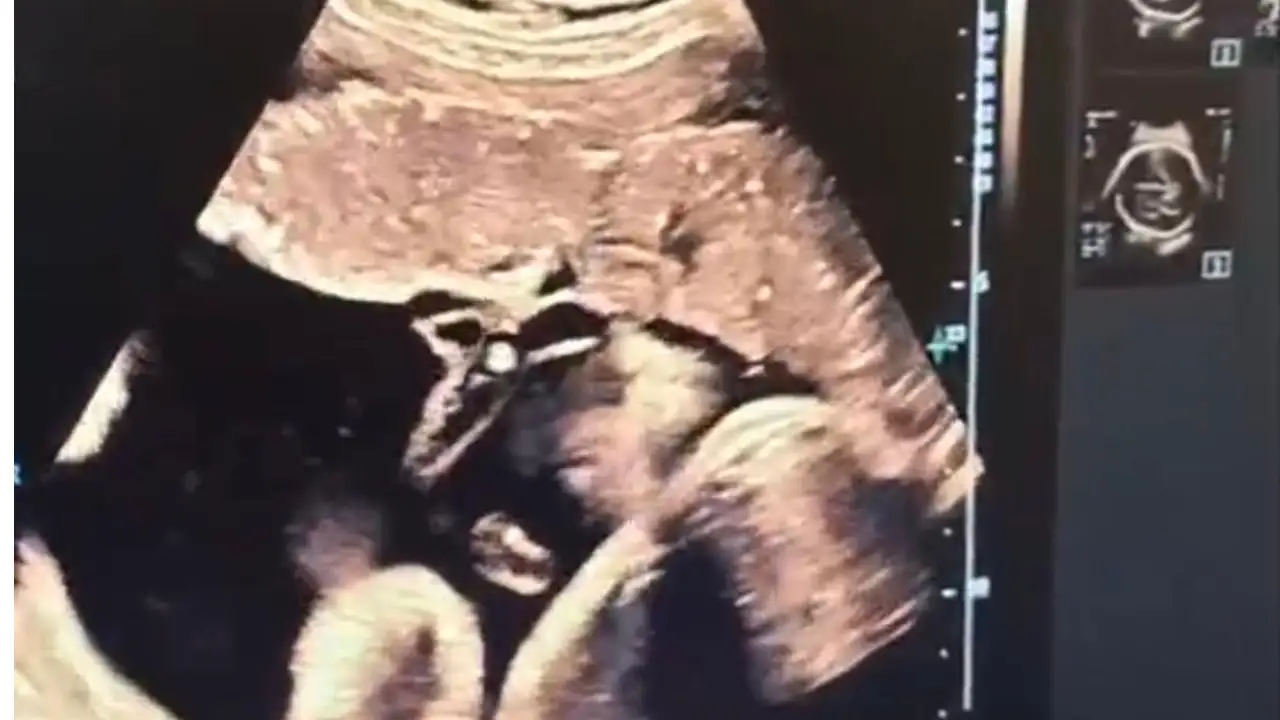

Bu kapsamda Kütahya Şehir Hastanesi’nde anne karnındaki bebeğe doğrudan kan nakli (İntrauterin Fetal Kan Transfüzyonu) operasyonu başarıyla gerçekleştirildi.

Anne karnındaki bebeğe doğrudan kan nakli operasyonunu anlatan Dr. Akkuş, halk arasında "anne karnında kan nakli" olarak bilinen bu işlemin bebeğin anne karnındayken ciddi kansızlık (anemi) yaşaması durumunda uygulandığını ve yaşam kurtarıcı bir müdahale olduğunu söyledi.

Ultrason eşliğinde, anne karnından ince bir iğne ile bebeğin göbek kordonuna girildiğini belirten Dr. Akkuş, “Önce bebeğin kan değerleri ölçülüyor, ardından eksik olan miktar kontrollü bir şekilde naklediliyor. Lokal anestezi altında, steril şartlarda yapılan işlem yaklaşık 30-45 dakika sürüyor.” diye konuştu.